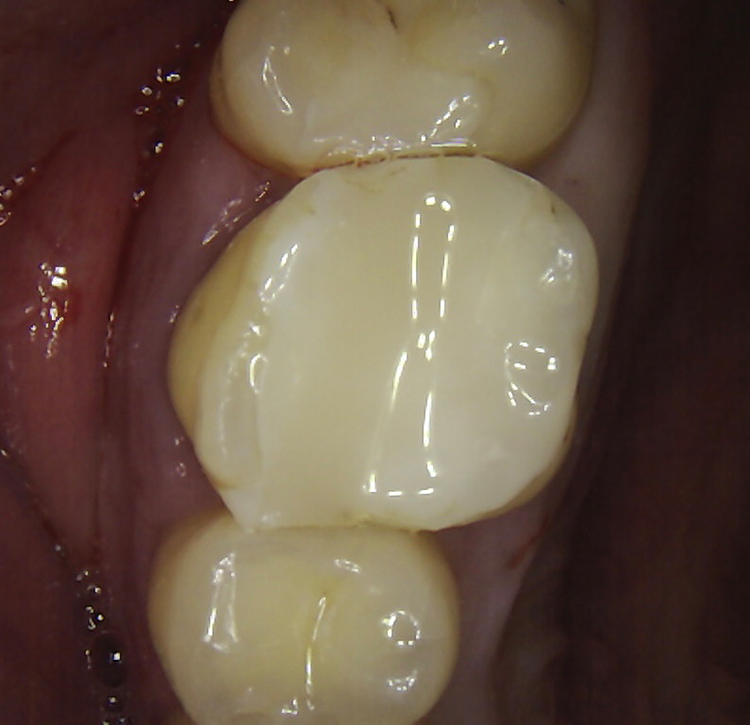

Abb. 2: Repräsentativer Fall von ABH Grad B Septus Typ II. a) Ansichten vor der Installation. Röntgenaufnahme der periapikalen Läsion an einem wurzelkanalbehandelten Molaren und klinische Ansicht der Typ-II-Socket nach der Extraktion. b) Die Ansichten nach der Installation zeigen das Implantat innerhalb des interradikulären Septums und das über dem Implantat platzierte A-PRF. c) Nachuntersuchungen nach 10 Tagen bzw. 2,1 Monaten. Die Röntgenaufnahme zeigt die Knochenbildung zwischen der Sinusmembran und dem apikalen Teil des Implantats. d) Jüngste Nachuntersuchung nach Einsetzen der Prothese.

Abb. 3: Repräsentativer Fall von Grad A Typ I. a) Präoperative Ansicht. Röntgenbild der periapikalen Läsion an einem wurzelkanalbehandelten Molaren. Die Höhe des Alveolarknochens zeigt Grad A an. b) Klinische und radiographische Ansicht der Implantatinsertion unter Verwendung einer Einheilscheibe mit großem Durchmesser (6×8 mm). A-PRF wurde um das Implantat und unter der Scheibe platziert. c) Nachuntersuchung nach 5,9 Monaten vor und nach der Zementierung und Aufbereitung. d) Jüngste Nachuntersuchung nach Einsetzen der Prothese

Die SDS-Zirkoniumdioxidimplantate wurden mit zementierten Pfosten weiter aufbereitet (Abb. 1d, 3 und 4c) und nach 4,74 + 0,95 Monaten Einheilzeit mit endgültigen Kronen versorgt. Die Balkonform ermöglichte ein natürliches Emergenzprofil, das die definitiven Kronen wie die Standardform ausrichtete sowie die Gesundheit des Weichgewebes und die Osseointegration förderte. Bei jeder Nachuntersuchung wurden Stabilität des Implantats, Zustand des umgebenden Gewebes und Vorhandensein von Zahnstein beurteilt.